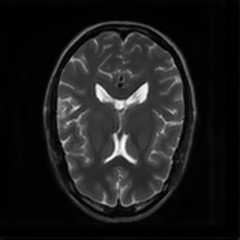

Limited by imaging systems, the reconstruction of Magnetic Resonance Imaging (MRI) images from partial measurement is essential to medical imaging research. Benefiting from the diverse and complementary information of multi-contrast MR images in different imaging modalities, multi-contrast Super-Resolution (SR) reconstruction is promising to yield SR images with higher quality. In the medical scenario, to fully visualize the lesion, radiologists are accustomed to zooming the MR images at arbitrary scales rather than using a fixed scale, as used by most MRI SR methods. In addition, existing multi-contrast MRI SR methods often require a fixed resolution for the reference image, which makes acquiring reference images difficult and imposes limitations on arbitrary scale SR tasks. To address these issues, we proposed an implicit neural representations based dual-arbitrary multi-contrast MRI super-resolution method, called Dual-ArbNet. First, we decouple the resolution of the target and reference images by a feature encoder, enabling the network to input target and reference images at arbitrary scales. Then, an implicit fusion decoder fuses the multi-contrast features and uses an Implicit Decoding Function~(IDF) to obtain the final MRI SR results. Furthermore, we introduce a curriculum learning strategy to train our network, which improves the generalization and performance of our Dual-ArbNet. Extensive experiments in two public MRI datasets demonstrate that our method outperforms state-of-the-art approaches under different scale factors and has great potential in clinical practice.